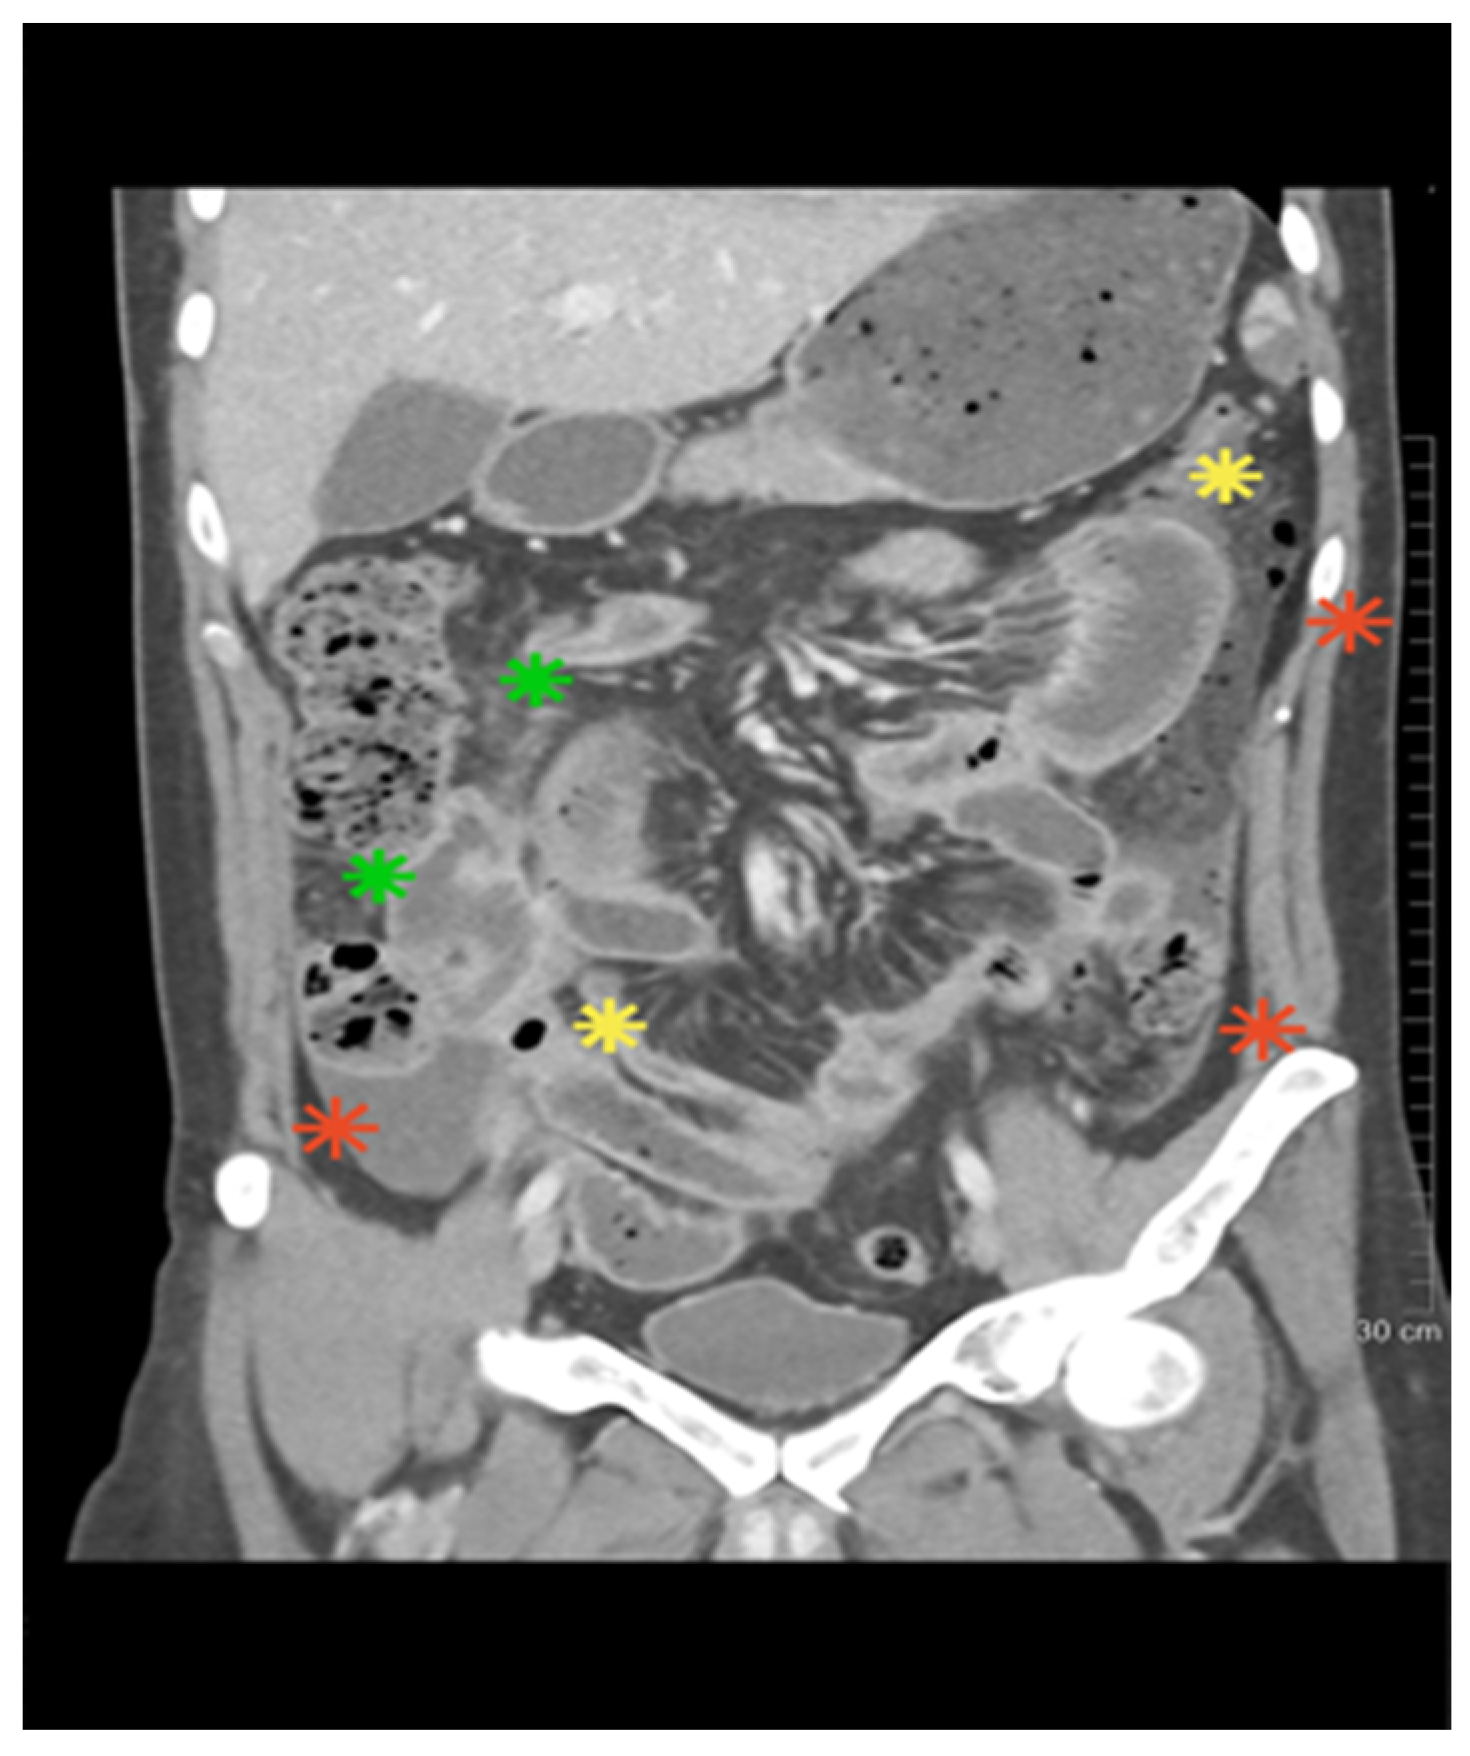

| Gastrointestinal perforations | Characteristic, esp. ileocecal/jejunal | Exceedingly rare (<10%) | 4 jejunal perforations | Decisive for BD |